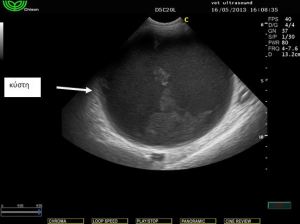

Ευρήματα: Στον υπέρηχο εντοπίστηκε μικρή παρουσία ασκητικού υγρού και μία μάζα στρογγυλή σαφώς περιγεγραμμένη χωρίς να δείχνει να έχει πρόσφυση σε κάποιο όργανο. Το τοίχωμά της φαινόταν αρκετά παχύ και στο εσωτερικό υπήρχε παρουσία παχύρρευστου υγρού. Στη διαφορική διάγνωση υπήρχε η υποψία για κάποιο απόστημα της περιτοναικής κοιλότητας, κύστη του μεσεντερίου και η δίλοβος εντερική κύστη (intestinal duplicated cyst). Μετά από χειρουργική εξαίρεση βρέθηκε πως η κύστη αυτή ήταν κολλημένη πάνω στο παχύ έντερο από την μία πλευρά και από το μεσεντέριο από την άλλη. Το περιεχόμενο ήταν μία άμορφη ουσία παχύρρευστη. Το τοίχωμα της κύστης έμοιαζε με το τοίχωμα του εντέρου. Η διάγνωση τέθηκε τελικά ως δίλοβος εντερική κύστη.